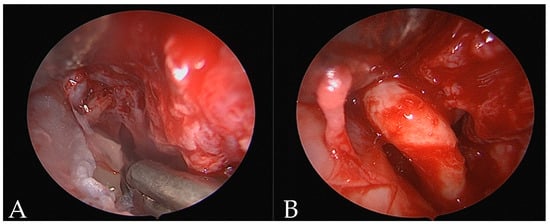

In 2022, the mesiodens removal was performed through an endoscopic nasal approach. Access via the nostrils was performed with a vertical hemitransfixion incision through the right side of the membranous septum. Dissecting scissors and Cottle elevators were then used to develop a sub-mucoperichondrial plane and dissected posteriorly to reveal the quadrangular cartilage. The robust mucoperichondrial flap was elevated and raised through the same incision after a second flap on the contralateral side. On the floor of the nasal fossa, an endoscopic osteotomy with a microdebrider was performed and by a 0-degree Hopkins rod endoscope, the mesiodens were shown. Surrounding the tooth, there was chronic inflammatory tissue. A twisting movement was employed to remove the mesiodens; once the tooth was luxated, the mesiodens would be grasped and extracted through the nostrils (Figure 2) followed by bleeding control. The mucoperichondrial flaps were laid back into position against the septum and sutured in Vicryl 3/0. Nasal packing was placed in both nasal fossae (Merocel, Medtronic, Mystic, CT, USA) to support the septal mucoperichondrial flaps and minimize the risk of septal hematoma formation. The extracted mesiodens was 14 mm in length, had a short cone-shaped root with a dilaceration at the apex, and a crown with incisor and canine teeth characteristics. The patient was discharged on the same day. The postoperative healing was uneventful. The pack was removed on the fifth postoperative day without any complications and the postoperative care consisted of a five-day course of Amoxicillin antibiotics and nonsteroidal anti-inflammatory drugs.

Figure 2. Endoscopic nasal view (A,B).